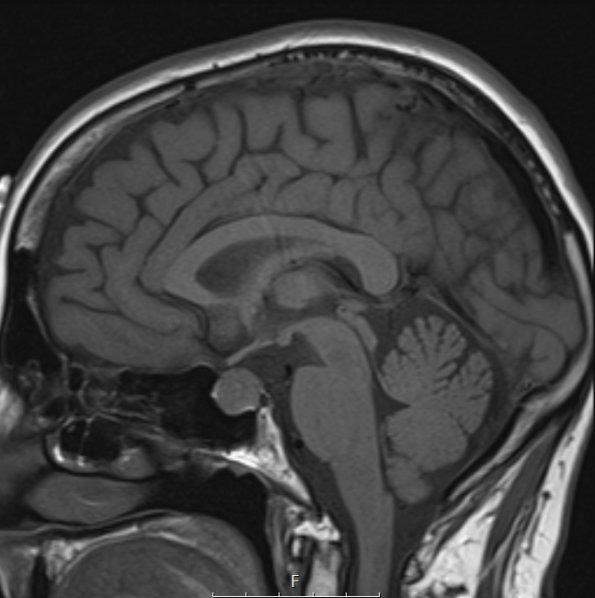

4A3C The location of the T1-weightted tumor is shown in sagittal section.